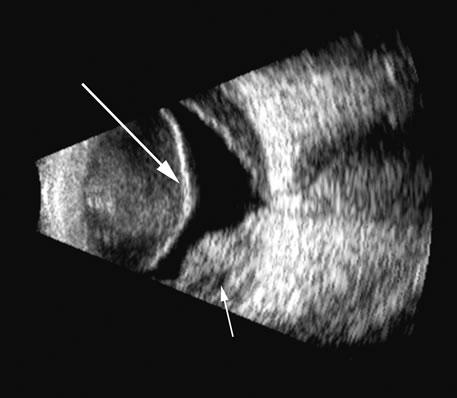

Malignant melanoma varies in its ultrasound presentation from a relatively homogeneous to heterogenous lesion on B-scan. The typical uveal melanoma absorbs sound so that the posterior section is relatively less echoic than the anterior aspect, producing a gradually decreasing amplitude, often to baseline on the A-scan (Fig. 21).

Fig. 21. An ocular tumor at the posterior pole showing the smooth convex border and solid internal reflectants typical of a melanoma.

Melanomas also have varying amounts of melanin, a highly acoustically reflective pigment. As noted, melanomas characteristically show high reflectivity anteriorly, with decreasing reflectance as the sound traverses the tissue. This produces the decreasing amplitude posteriorly in the tumor seen on A-scan and gray-scale B-scan. This effect often enhances the anterior scleral boundary. The posterior tumor border is thus measured as the first “rising” echo from the tumor decline, and it is most easily seen and accurately identified on B-scan.27

Metastatic carcinoma is more heterogeneous, producing a more uniform A-scan amplitude of roughly 50% to 80% of the “scleral” echo amplitude (see below) behind the tumor (Fig. 22). Hemangioma is a very highly reflective tumor with high amplitude all the way through the tumor of 80% to 100% of scleral echo amplitude (Fig. 23).

Fig. 22. Some hemangiomas and metastatic carcinomas may simulate a melanoma. They are differentiated on the basis of a very high amplitude internal echo complex for the hemangioma, a moderately low but sustained echo pattern for the metastasis, and an A-scan with decreasing reflectance as the tumor thickness is traversed. In the center scan of a melanoma, note the double anterior layer caused by edema fluid underlying the crest of the melanoma (arrow).